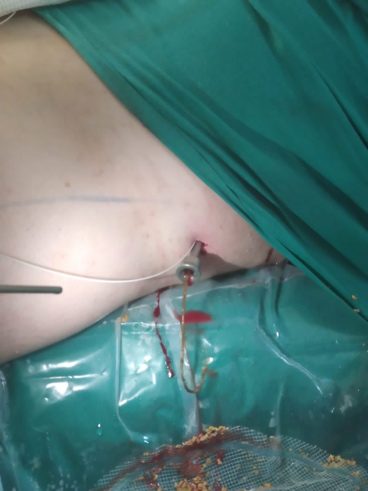

Пациент перемещен из литотомического положения в положение на спине. Под рентген контролем пунктирована нижняя чашка левой почки. Проводник проведен в лоханку и далее в верхнюю чашку. Установлен страховой проводник. Нефростомический ход поэтапно бужирован Выполнена нефроскопия, при которой определяется камень с желтоватой поверхностью в нижней чашке и лоханке левой почки, размерами 32х34 мм. Камень поэтапно фрагментирован с помощью лазерного литотриптера, фрагменты камня, детрит и внутренний мочеточниковый стент удалены эндоскопическими щипцами через нефростомический ход. Рентген контроль, в ЧЛС левой почки установлена нефростома.

Фрагменты камня, детрит и внутренний мочеточниковый стент удалены через нефростомический ход (рис. 8, рис. 9).